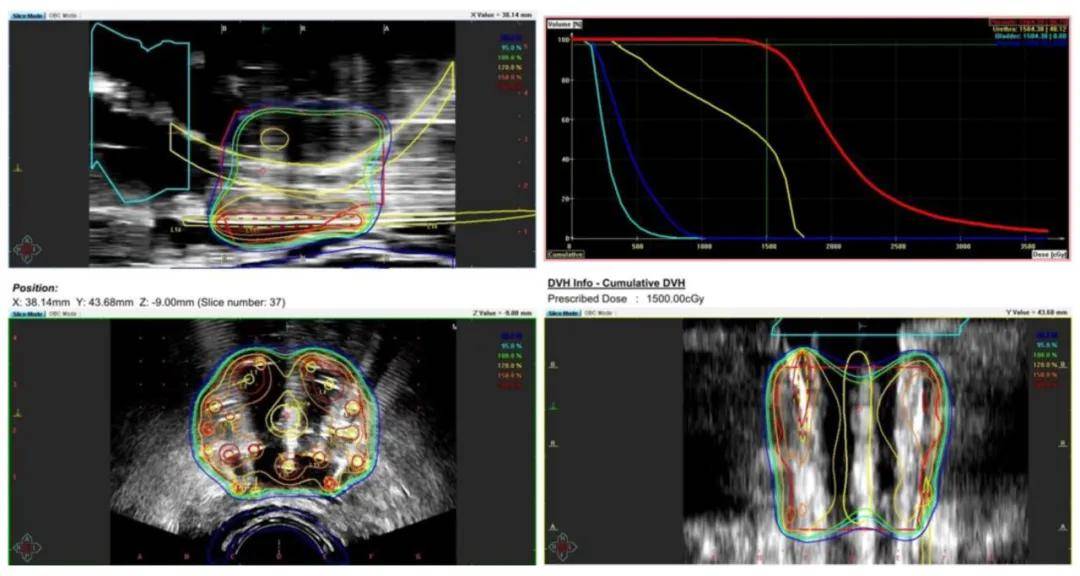

本研究提出一种针对广泛转移性前列腺癌的综合治疗方案。一名57岁男性患者因PSA水平升高入院 (图1),经全面评估后,先接受比卡鲁胺治疗,并通过PET/PSMA等影像学检查明确癌症分布。随后,患者接受雄激素剥夺疗法及多西他赛化疗。因疾病仍有活动迹象,故采用放疗巩固,包括针对前列腺和转移淋巴结的远程放疗 (图2) 及前列腺的高剂量率近距离放疗 (图3)。

患者初始PSA高达280 ng/mL,前列腺活检确诊为腺癌,Gleason评分7,WHO分级3。CT显示广泛盆腔淋巴结转移,PET/PSMA影像 (图4) 揭示前列腺及淋巴结高代谢活性。患者被诊断为cT2N1M1a期前列腺癌。经多西他赛化疗,PSA水平有所下降,但CT仍示广泛转移。随后进行放疗,PET-CT (图5) 显示前列腺及淋巴结仍具活性。放疗后,患者PSA降至检测限下,实现完全生化缓解,此疗效经随访影像及临床评估确认。